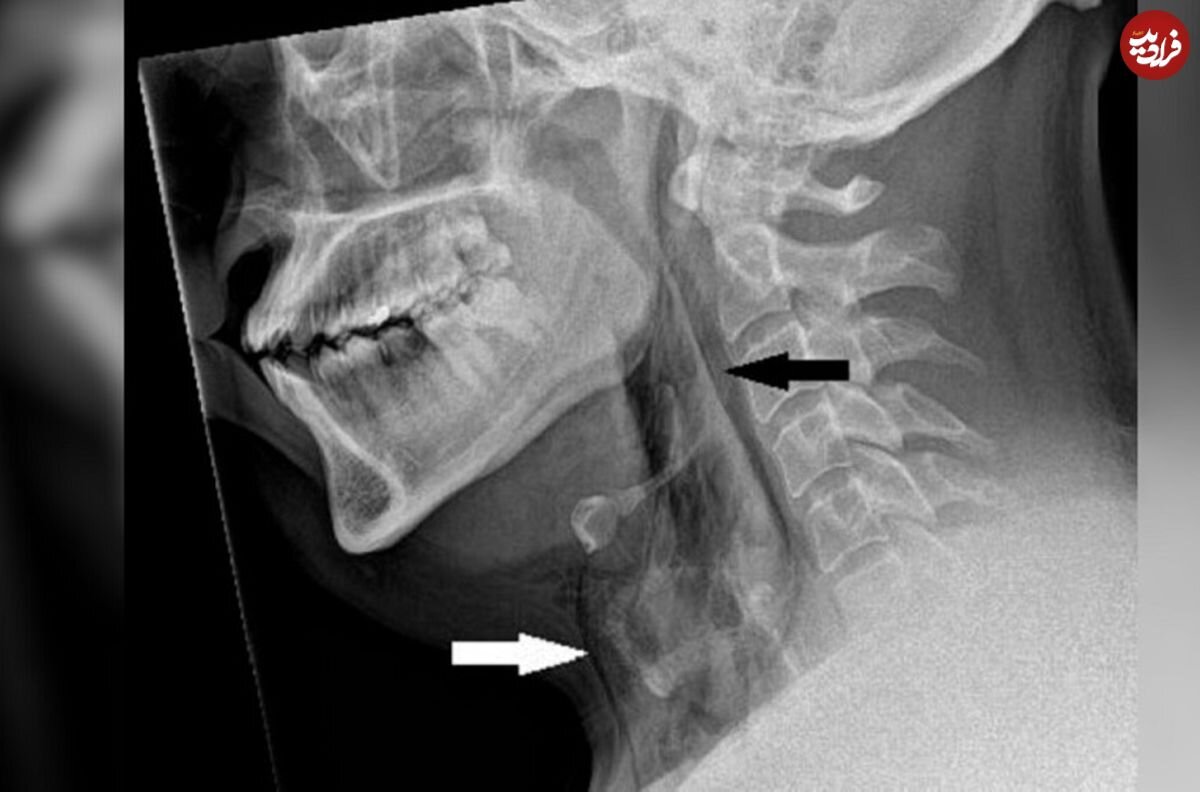

عکسبرداری با اشعه ایکس از گردن نشان داد مرد مبتلا به آمفیزم زیرپوستی است، بیماریای که در آن، هوا زیر عمیقترین لایههای بافت زیر پوست گیر میکند. توموگرافی کامپیوتری (سیتیاسکن) نشان داد پارگی بین استخوانهای سوم و چهارم یا مهرههای گردن او رخ داده است. هوا نیز در فضای قفسهسینه بین ریههای او جمع شده بود. پزشکان به این نتیجه رسیدند که پارگی ناشی از افزایش سریع فشار در نای هنگام عطسه با بینی فشرده و دهان بسته است.